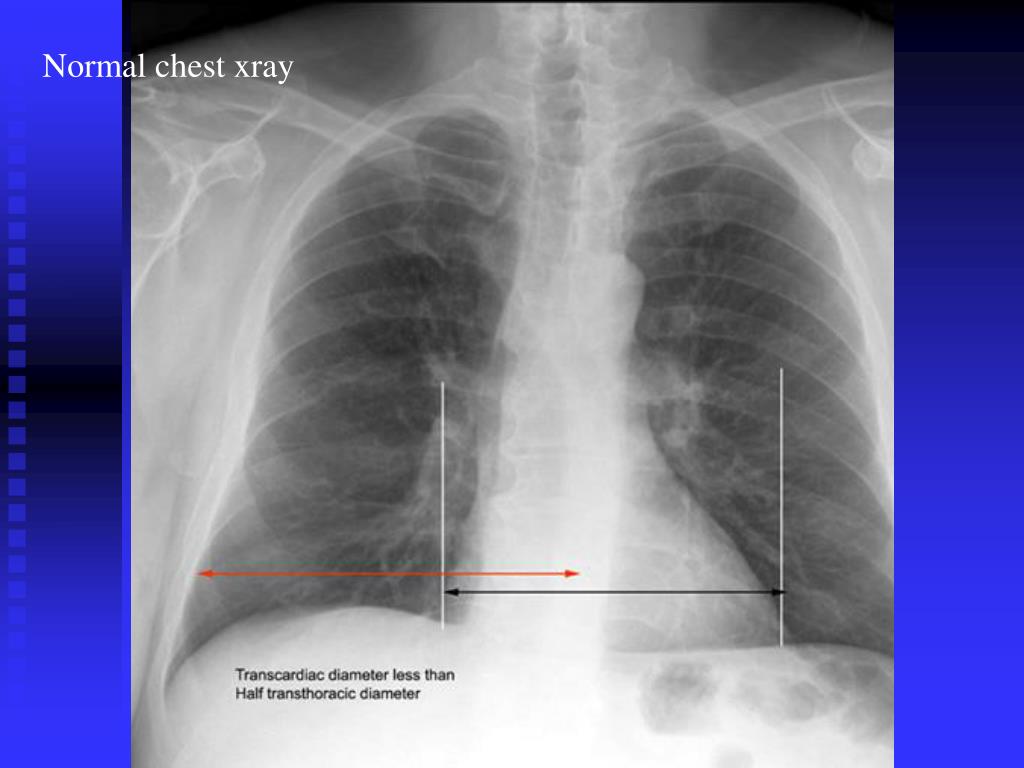

Contrast dye can be injected into your blood vessels (to show the vessels), it can be ingested. 5,8 water (soft tissue) density looks white to gray on the cxr. The air in your lungs shows up as black.

This is because of high. The constant air pocket in the stomach is the gastric bubble. Very dense material such as metal or contrast material is represented as white. Black color appears because of air.

But the basics of chest xray here will guide you through various aspects, including counting ribs, pa vs ap view, inspiratory vs expiratory xray, erect vs supine, lucency and. In consolidation the alveolar spaces become filled with fluid making them appear white, whereas the airways retain air making them appear black. Contrast dye can be injected into your blood vessels.

Mri urography changing magnetic field produces images of the kidney and surrounding structures in three planes of the body. The four basic densities on a cxr are bone (or metal), water (soft tissue), fat, and gas (air). It was observed that color signal may appear within the fluid collection in the pleural space. The constant air pocket in the stomach.

You can see it on xray and hear it on percussion. Fat and muscle appear as shades of gray. Asymmetry of lung density is represented as either abnormal whiteness (increased density), or abnormal blackness (decreased density). Xray green what is an air pocket in the stomach? This is because of less density.